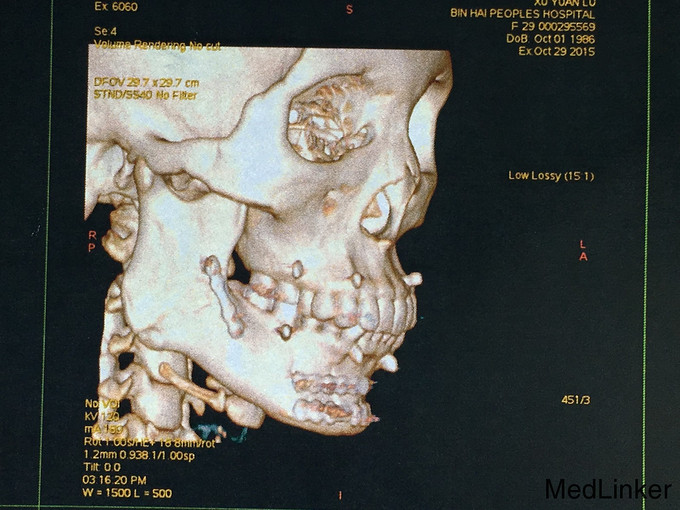

查体:神志清楚,右下颌体部见长约2.0cm开放创口,张口度1.5cm,咬合关系紊乱,右下唇麻木感,43,44间见明显骨折线,异常动度,48松动II,牙龈撕裂,右下颌肿胀,右侧髁状突冲击试验减弱,上颌骨无异常动度,于无异常。 辅查:CT,右下颌骨颏部及下颌角不骨折。

诊断:右下颌骨颏部及下颌角不骨折 治疗:右下颌骨颏部及下颌角部骨折经口内切开复位内固定。